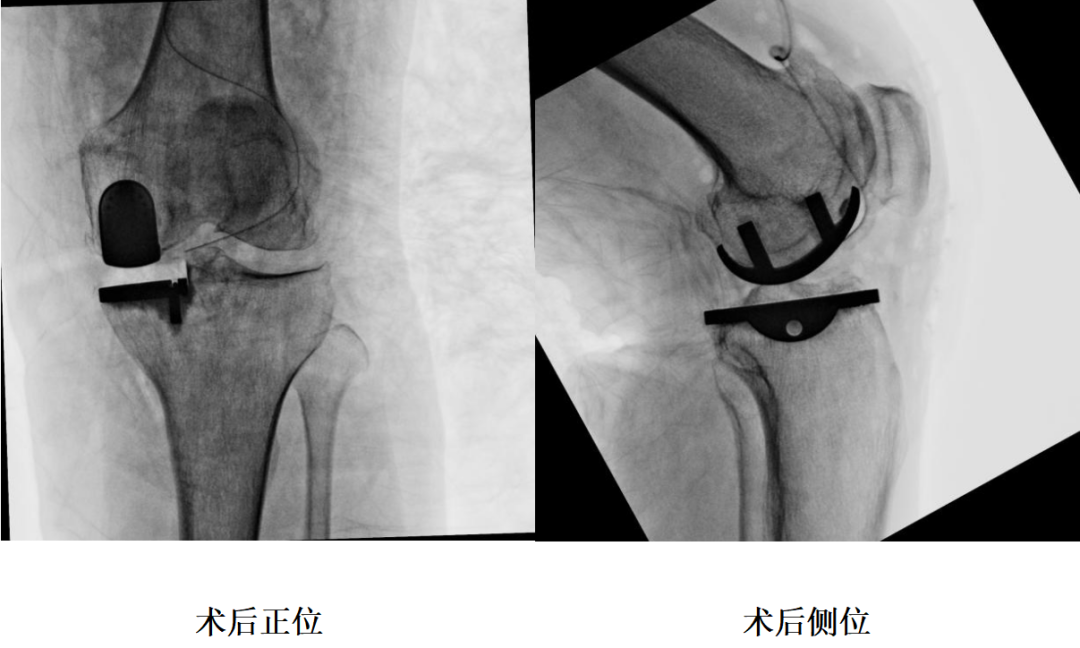

四、术后X片

17、透视:假体位置(Excision of osteophytes )